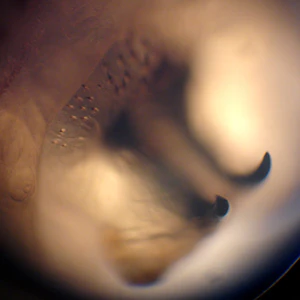

A 75-year-old man developed a lesion on his right forearm. The lesion developed approximately one month after returning from a trip to Costa Rica. The patient’s attending physician removed what appeared to be a fly larva. The larva was sent to the hospital’s Microbiology Department for further identification. Figure A and B show the ventral and lateral sides of the larva, respectively. Figure C shows a close-up of the mouthparts. Figure D shows a close-up of the cuticular spines. What is your identification? Based on what criteria?

Figure D